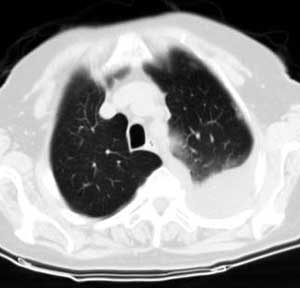

测ct值3-6hu,

既然ct值是3-6hu,还不如考虑包裹性积液。

请上传纵隔窗。目前还是支技包裹性积液(明显梭形),即使是间皮瘤并积液也少梭形的。

从图片看,包裹性积液好象更合理,梭形,ct值3-5hu(在哪看到的?);胸膜间皮瘤如此规则,不多见。

左侧背部胸膜肥厚,伴包裹性积液,不考虑间皮瘤.

同意以上各位的高见,首先考虑包裹性积液,1.胸膜间皮瘤积液量一般较大,以游离性积液更为常见,2.可以看到增厚的胸膜结节